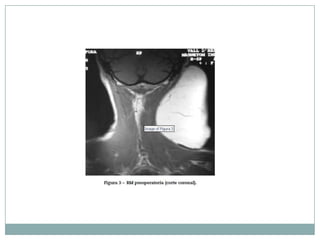

La aparición de lipomas gigantes a nivel cervical es

infrecuente. Es necesaria la realización de pruebas de

imagen para una correcta localización anatómica y

establecer relaciones con las estructuras vecinas.